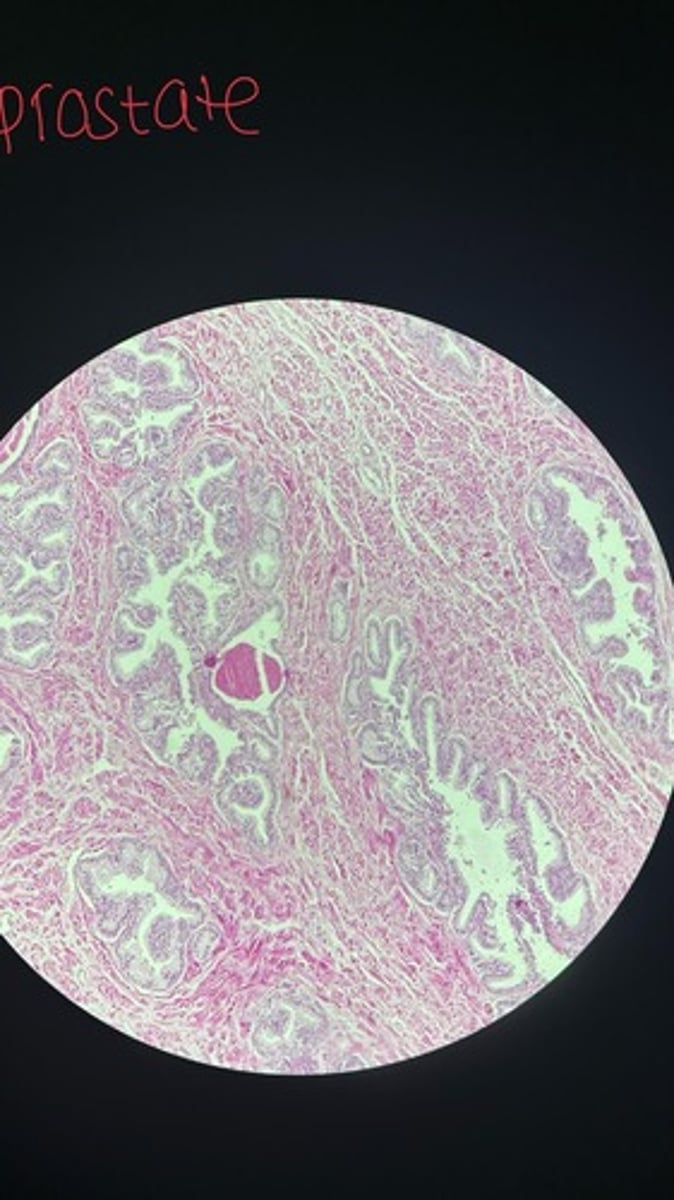

Prostate HE

Prostate HE

Prostate HE

Prostate HE